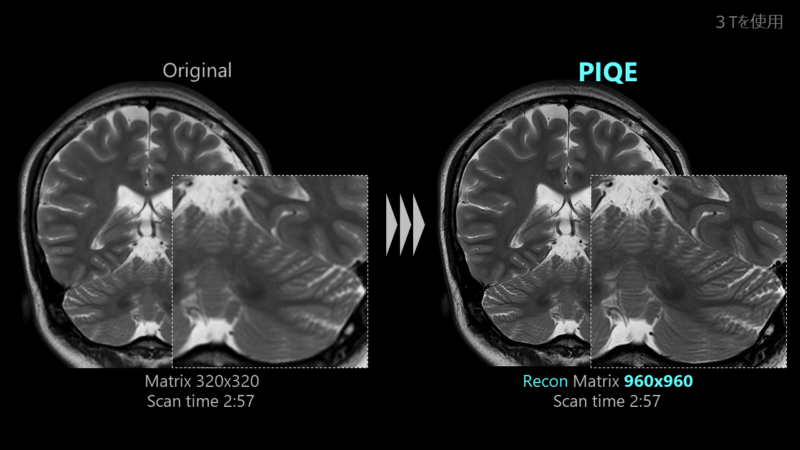

Năm 2018, Canon là một trong những công ty đầu tiên phát triển công nghệ DLR và phát hành Công cụ Clear-IQ thông minh nâng cao (AiCE), một công nghệ cải tiến SNR được thiết kế bằng cách sử dụng máy học sâu. Vào năm 2023, chúng tôi sẽ phát hành PIQE như một công nghệ thế hệ tiếp theo sử dụng công nghệ học sâu, vốn đã phát triển hơn nữa dựa trên công nghệ mà chúng tôi đã phát triển.